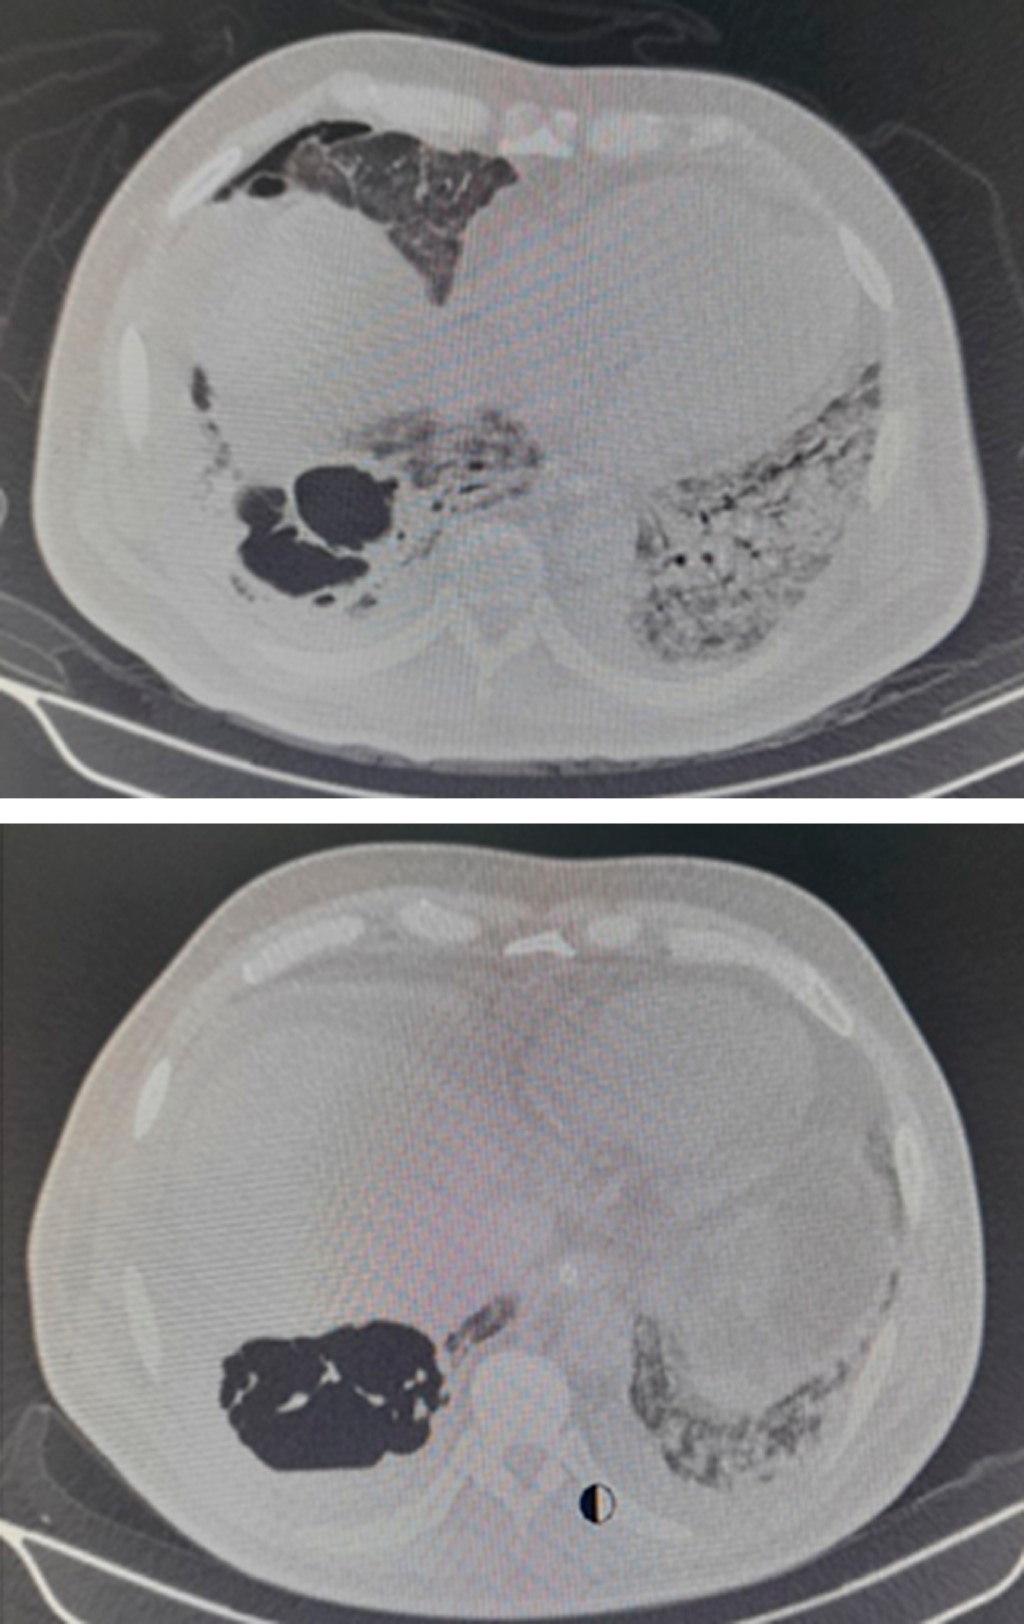

Se trata de un hombre de 56 años sin antecedentes de importancia, el cual presenta cuadro de fiebre, tos, rinorrea, malestar general. El día dos de iniciado el cuadro clínico se realiza reacción en cadena de la polimerasa (PCR) para el SARS-CoV-2 cuyo resultado fue positivo, recibe tratamiento domiciliario. El día tres de iniciado el cuadro es trasladado a un hospital privado por persistir con disnea y desaturación requiriendo administración de oxígeno suplementario. El día 10 de iniciado el cuadro muestra datos de dificultad respiratoria e hipoxemia ameritando intubación orotraqueal e inicio de ventilación mecánica por presentar síndrome de insuficiencia respiratorio agudo (SIRA) severo de acuerdo a la clasificación de Berlín (PaO2/FiO2 70 mmHg). Durante su estancia recibe tratamiento a base de levofloxacino, tocilizumab y dexametasona, por la mala evolución clínica requiere de parámetros altos de ventilación y apoyo con vasopresor. Se decide traslado a nuestro hospital 28 días después de haber iniciado el cuadro clínico. Es ingresado a terapia intensiva donde se le realizó traqueostomía percutánea por ventilación prolongada, permanece con requerimientos altos de fracción inspirada de oxígeno. El día 40 de iniciado el cuadro se documenta en radiografía de tórax imagen radiolúcida en tercio inferior derecho compatible con bulla pulmonar (Figura 1). Se realiza tomografía computarizada de tórax, la cual reporta área de atrapamiento aéreo con presencia de septos en su interior en segmento 10 del pulmón derecho (S10) compatible con bulla y neumotórax (Figura 2).

Figura 2